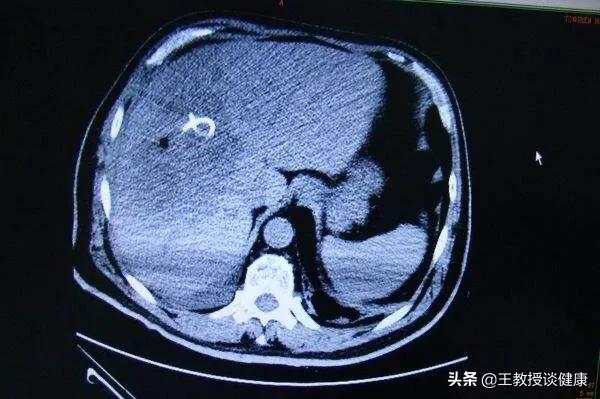

CT检查所见肝右叶肝脓肿影像

CT所见肝右叶肝脓肿明显液化影像